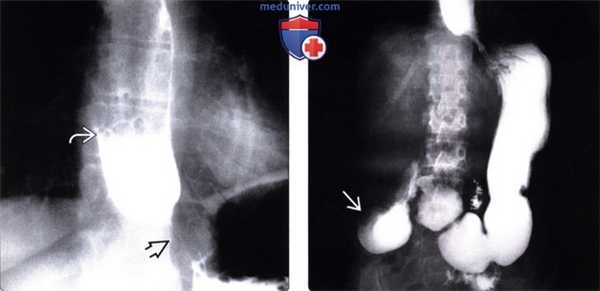

(Слева) На рентгенограмме пищевода, выполненной во время рентгеноскопии у мужчины 50 лет определяется отсутствие первичной перистальтики и глубокие, периодические третичные сокращения стенки пищевода. Просвет пищевода слегка расширен, видна стриктура в области пищеводно-желудочного перехода.

(Справа) На рентгенограмме, выполненной спустя два часа после рентгеноскопии этому же пациенту, определяется выраженное замедление прохождения контраста по тонкой кишке. Складки тощей кишки истончены и близко прилежат друг к другу, просвет кишки расширен, перистальтика выражена минимально: эти изменения являются классическими признаками «истощения» кишки.

(Слева) При рентгеноскопии с контрастом у женщины среднего возраста, страдающей склеродермией, определяется дилятация и атония пищевода с наличием тугой стриктуры в области пищеводно-желудочного перехода. Пищевод медленно освобождается от бариевой взвеси, даже в положении пациентки стоя: длительное время сохраняется уровень между взвесью сульфата бария и жидкостью.

(Справа) На рентгенограмме, полученной через некоторое время у той же пациентки, определяется выраженное расширение просвета второй части двенадцатиперстной кишки с резким переходом в сужение на уровне позвоночного столба. Двенадцатиперстная кишка является вторым наиболее часто поражающимся органом ЖКТ при склеродермии; на первом месте находится пищевод.

(Слева) На рентгенограмме, выполненной во время рентгеноскопии верхних отделов ЖКТ, определяется гастроэзофагеальный рефлюкс вследствие «зияния» нижнего пищеводного сфинктера. Первичная перистальтика пищевода отсутствует. Это относительно ранние изменения при склеродермии: ни стриктуры, ни язв еще не возникло.

(Справа) На рентгенограмме, выполненной этому же пациенту в положении лежа на спине во время рентгеноскопии верхних отделов ЖКТ, определяется обратный заброс бариевой взвеси в расширенный пищевод.